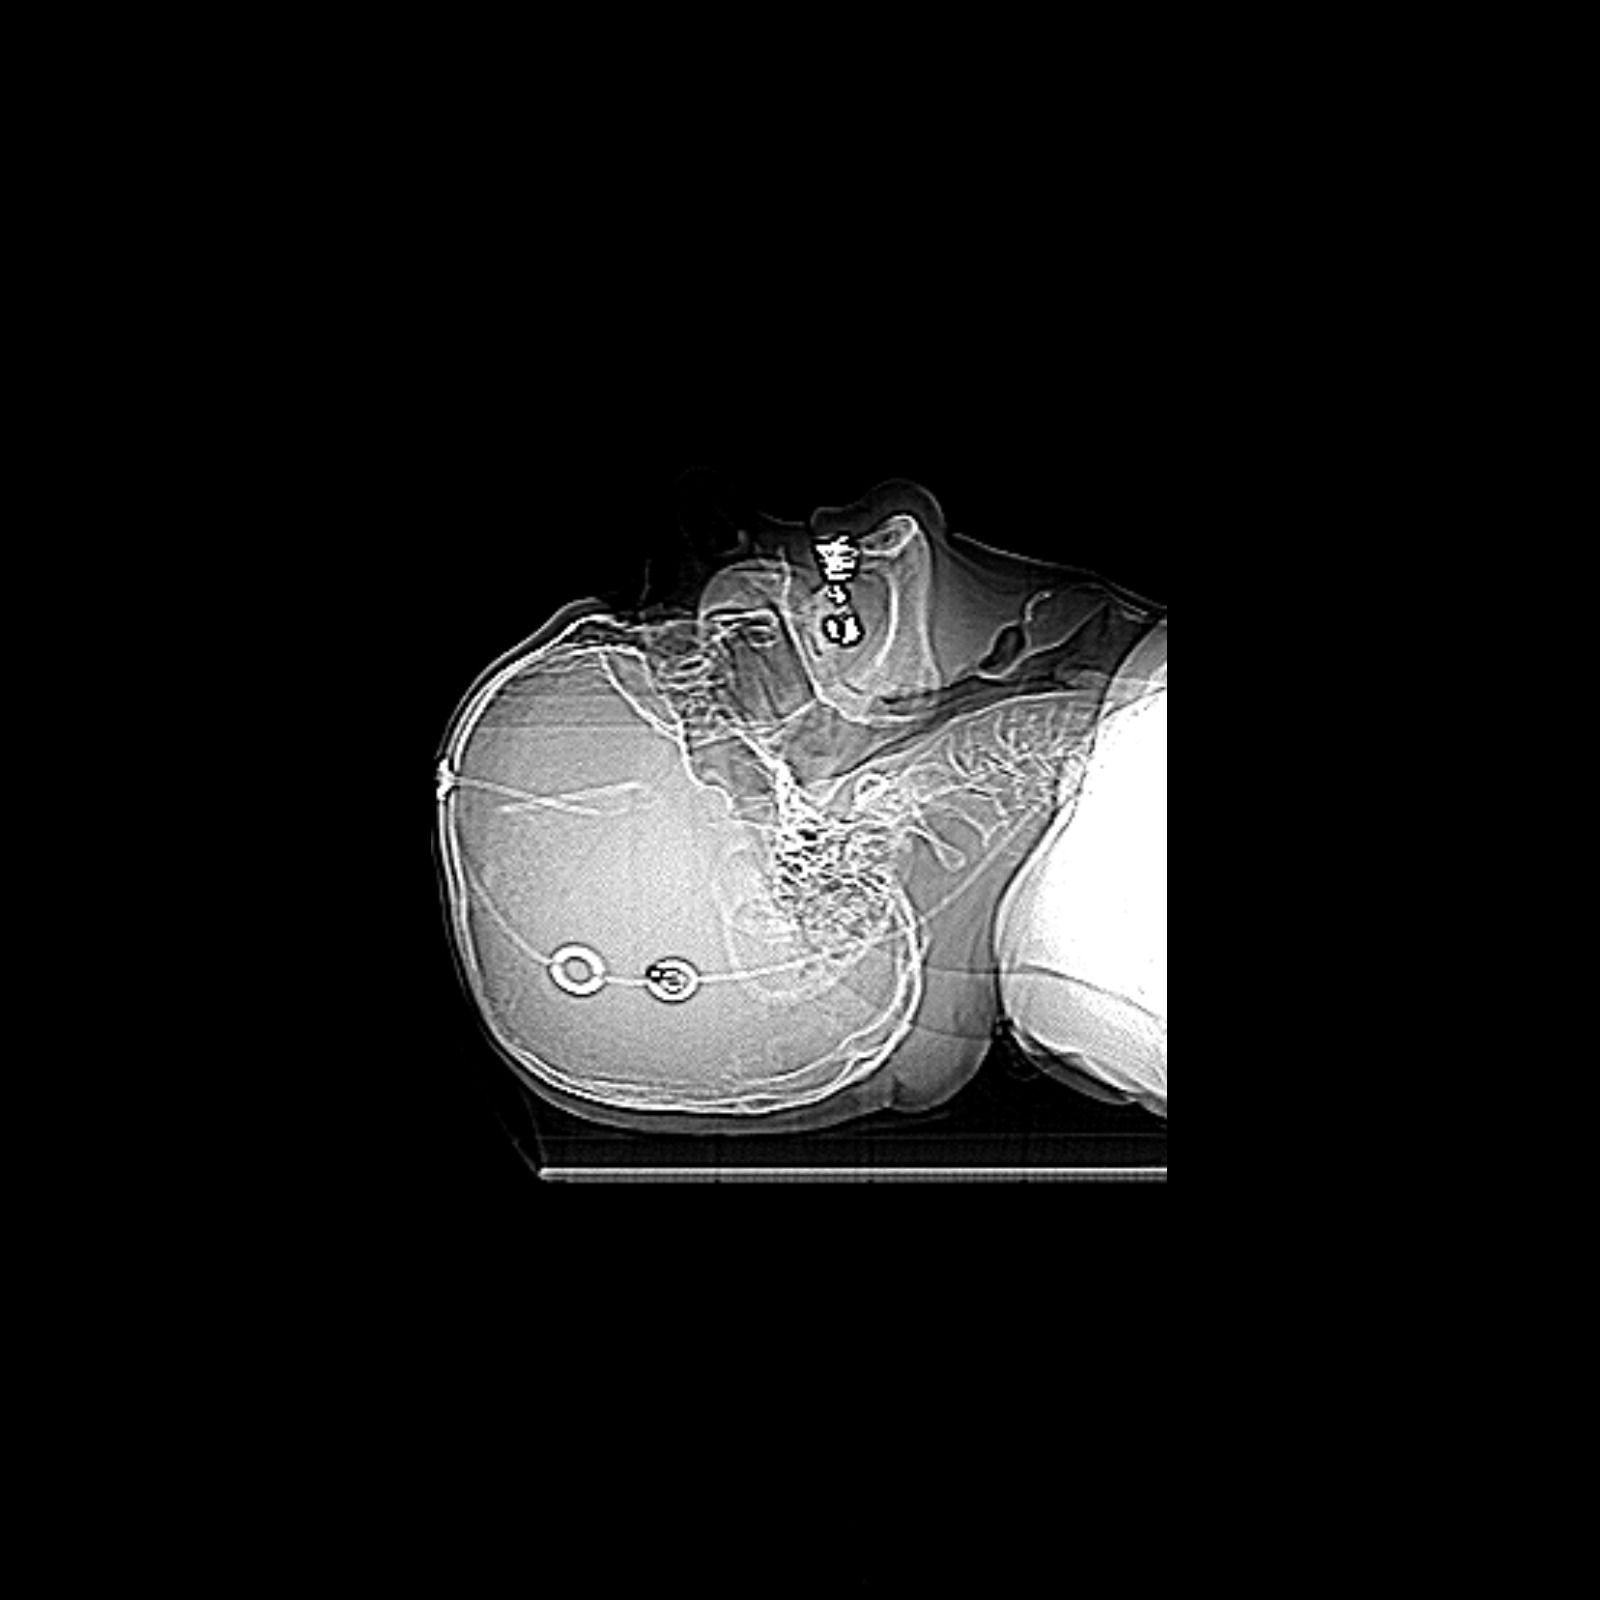

The literature on hydrocephalus treatment shows support for adjustable valves and devices which prevent the so-called "siphon effect". In our study, 21 probable iNPH patients were indicated to shunt surgery with the Miethke M.blue® adjustable gravitational valve. Outcomes at three months were measured using the following tests: Dutch Gait Scale, International Consortium on Incontinence Questionnaire (ICIQ-UI SF), SF12V2-Health Survey, Kiefer Scale, 3T MRI, and a neuropsychological testing battery. Preoperative parameters were studied for any signs of overdrainage risk. Valves were set according to the manufacturer's recommendations. Significant improvement at three months was seen in the Dutch Gait Scale, ICIQ-UI SF, Kiefer Scale, Mental Health Component of the SF12V2-Health Survey (MCS-12) and three neuropsychological tests: Rey-Osterrieth complex figure test (ROCFT 30 min), auditory verbal learning test (AVLT I-V) and the NKP version of verbal fluency test. Seven patients needed more than one adjustment of the valve. This subgroup significantly improved only in Walking Score and Step Score but the trend was toward significant improvement in other variables. Eight patients had subdural effusions that were completely managed with adjustments until the 3-month control. BMI was significantly lower in patients with ≥2 adjustments compared to those with a maximum of one adjustment. Implantation had low complication rates and no mortality. Initial results are promising, however, more studies are needed to provide rationale for gravitational valves in iNPH. We recommend increasing the initial valve setting by 2–4 cm H2O above manufacturer's recommendation, especially in lean patients.